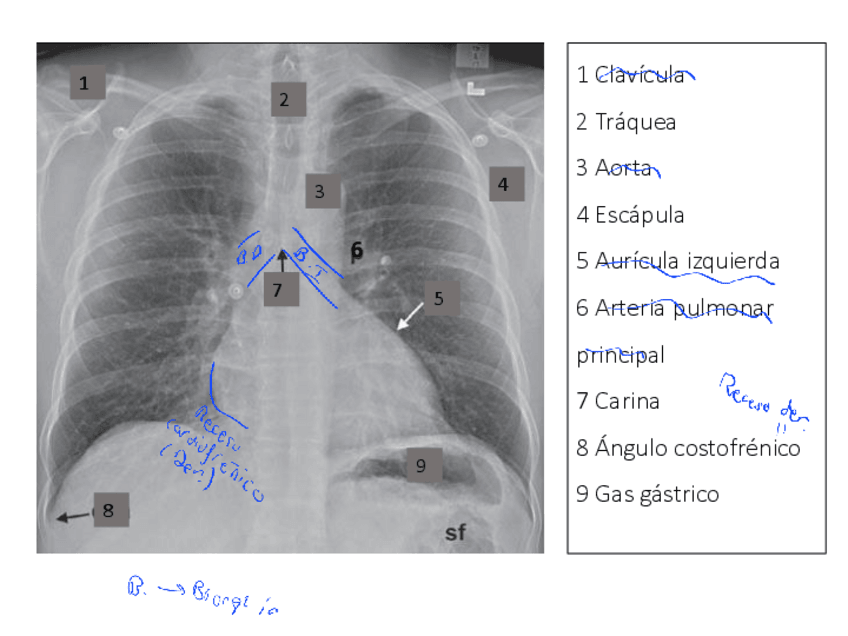

He publicado nuevos apuntes de Anatomía por la imagen: Imagenes-torax-Ap-RespiratorioTODAS-TECNICAS.pdf

27 páginas